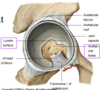

Is all the acetabulum an articular surface?

No

There are 2 parts to the acetabulm

- A lunate surface is the semicircular surface that is the weight bearing region and articular with the femur

- The acetabular notch & fossa are in the centre and are non- articular. This is roughened bone i with exposed trabeculae

What is the acetabular notch?

What fills this notch?

A depression in the margin of the acetabulum located anteroinferiorly.

It is bridged by a transverse ligament

What is located deep in the socket and fills irregularities in the hip joint socket/acetabulum?

A fat pad

Intra-articular but extra-synovial fat that has both a nerve and blood supply (source of pain and bleeding) and is also important in spreading the synovial fluid.